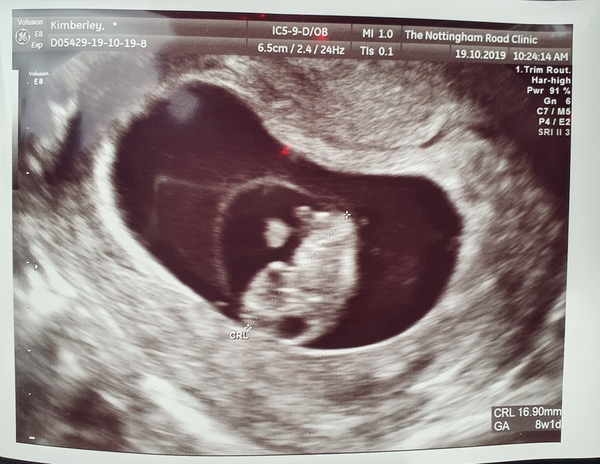

Emmacb82 · 19/10/2019 11:23

Scan went really well, measuring 8+5 which is bang on dates. Was so emotional seeing the little heart beating away. Hope everyone else’s either today or the next few days go ok xx

BeautyAndTheBump1 · 19/10/2019 12:09

Measuring perfect and healthy at 8+1 😭 I'm so relieved! Makes it feel much more real now. Just need to stick the photo on the toilet for when I'm being sick a million times a day for motivation 😂